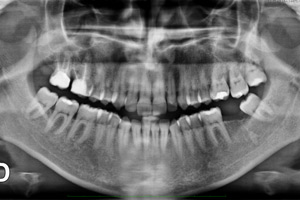

Ortopantomografia Digital

O paciente posiciona-se no ortopantomógrafo, imóvel enquanto são emitidos os Raios X movendo-se para tal o ortopantomógrafo em torno em torno do paciente (arcadas dentárias). Este exame é sempre feito por um técnico de radiologia podendo ou não ter a intervenção de um Médico (Radiologista, Dentista ou Estomatologista).